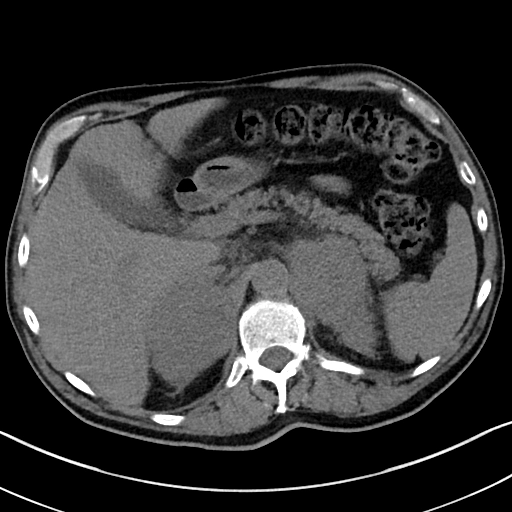

Carcinoma vỏ thượng thận (Adrenal cortical carcinoma)

Di căn tuyến thượng thận (Adrenal metastasis)